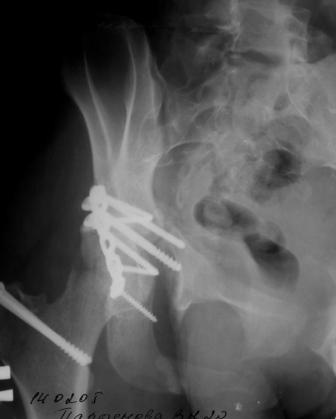

30/11/04 |  30/11/04 |  30/11/04 |  14/12/04 |  14/12/04 |  14/02/05 |  14/02/05 |  21/02/05 | Уважаемые коллеги! Случилось вторичное смещение вертлужной впадины после операции. Посоветуйте, что делать. Пациентка 18 лет. Травма 19.11.04. D.s.: Закрытыый Т-образный высокий перелом правой вертлужной впадины. Закрытый перелом м\мыщелкового возвышения левой б\берцовой кости. 9.12.04 операция - открытая репозиция, остеосинтез переломам вертлужной впадины. 30.12.05 выписаны на амбулаторное лечение с рекомендациями не вставать на правую ногу. 14.02.05 при контрольном осмотре на Р-граммах выявлено вторичное смещение передней колонны. Клинически подвывиха нет, имеется умеренная приводящая контрактура правого тазобедренного сустава, гипотрофия мышц н\конечностей. Госпитализирована в травмотделение. Выполнено КТ. Имеется смещение передней колонны кнутриЮ диастаз 8 мм. Посоветуйте пожалуйста, что предпринять в данной ситуации.

У больной имеется диастаз лонных и седалищных костей, то есть "разорвано" тазовое кольцо. В перспективе возможно образование ложного сустава на уровне основания лонной кости с болевым синдромом, поскольку седалищная кость не срастется.

Сустав-то как раз неплох, поскольку впадина почти вся конгруэнтна, по крайней мере вся нагружаемая часть, и подвывиха бедра нет. Артроз в перспективе тут, конечно, не исключить, но на первом плане проблема целости тазового кольца, т.е. нестабильное несращение, о чем А. Рунков писал. На седалищной дефект, и если и разошедшееся основание лонной не срастется, то болезненные проявления могут быть сразу после начала нагрузки, как ее не отсрочивай.